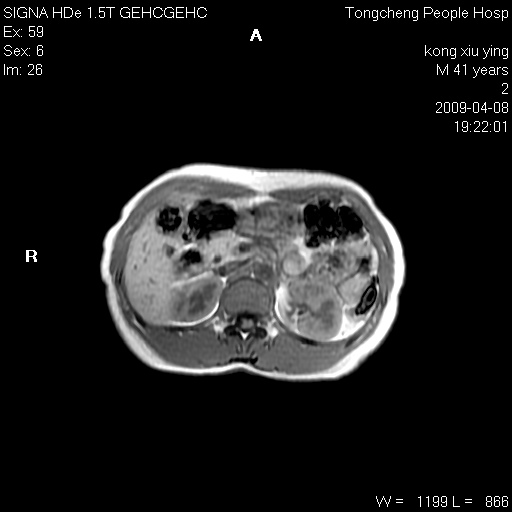

标题: CL1008:【经典】胆囊石榴籽样结石。

女,41岁。健康体检——彩超提示:胆囊显示不清。平素健康,无不适感。

腹部mr扫描及mrcp,图像如下: